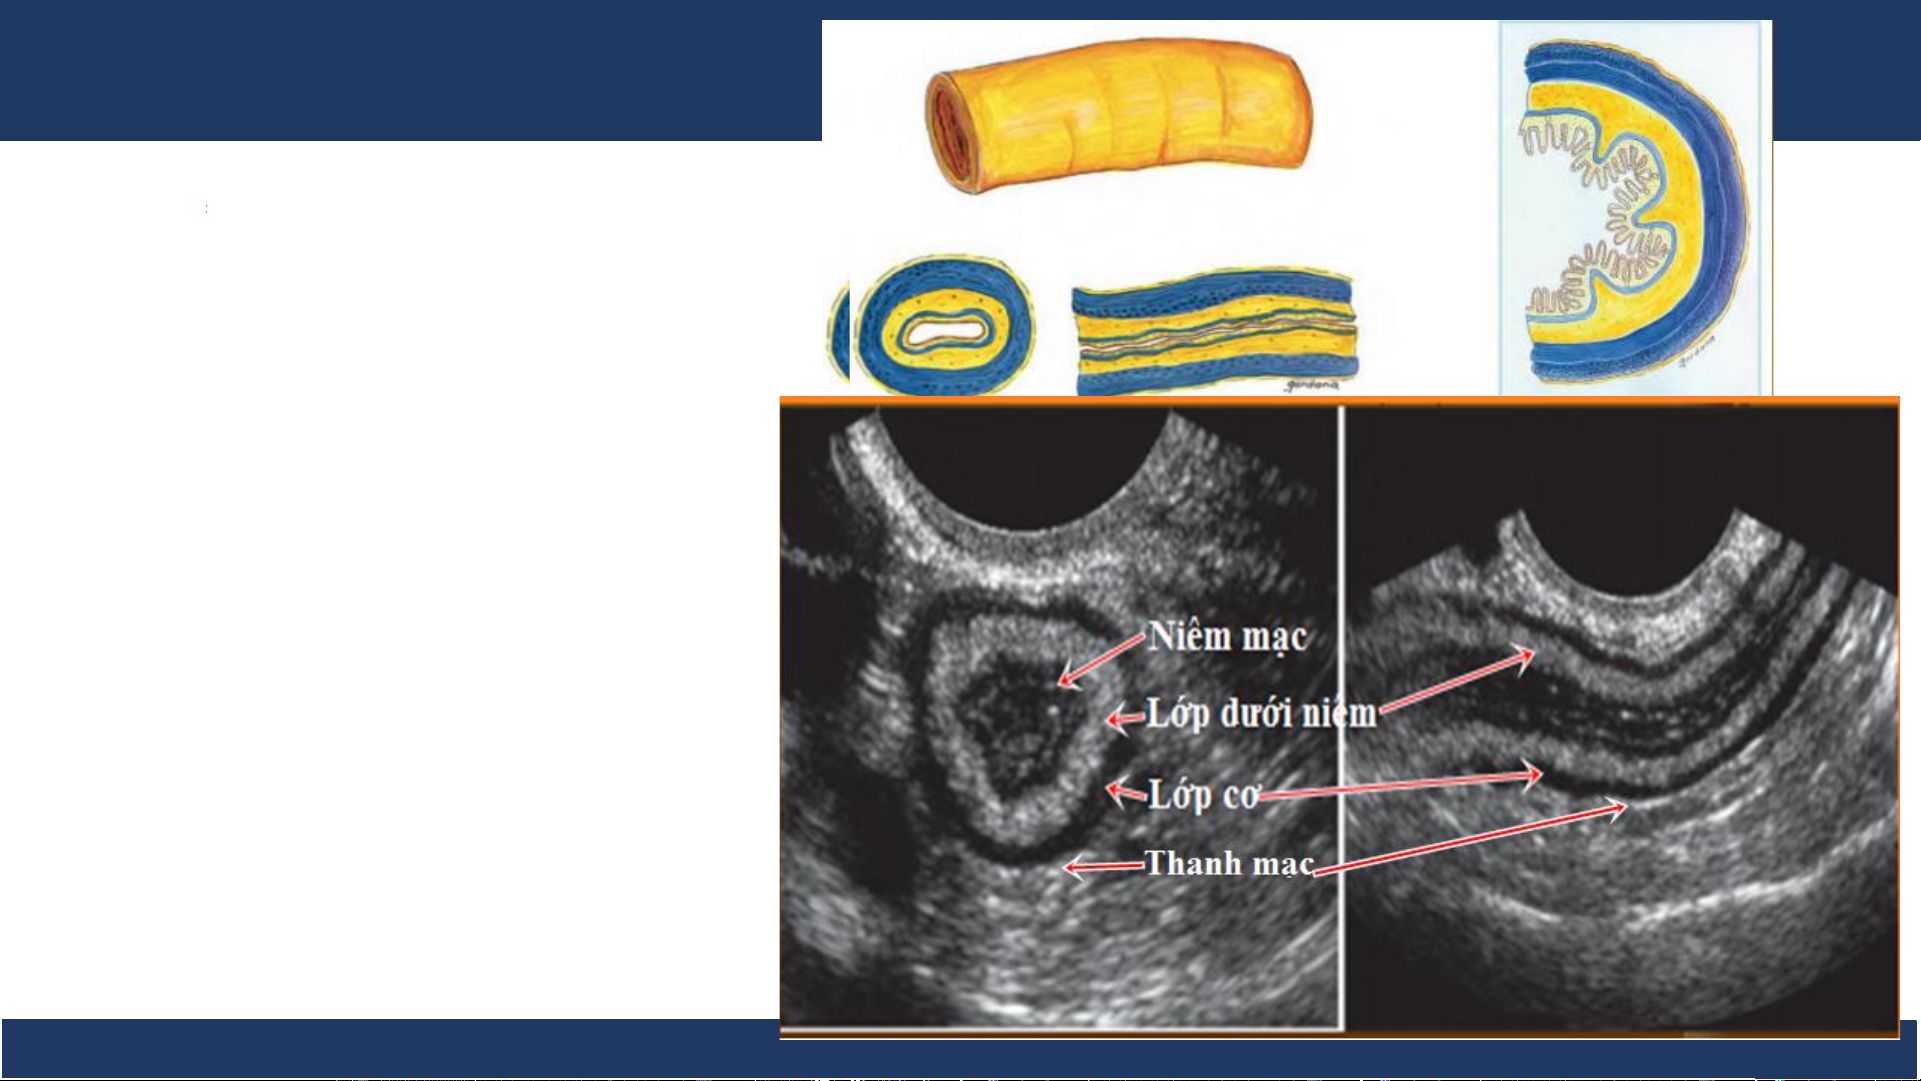

Trên siêu âm có thể thấy được 3-5 lớp:

• Niêm mạc phản âm dày • Cơ niêm phản âm kém

• Lớp dưới niêm phản âm dày • Lớp cơ phản âm kém

• Lớp thanh mạc phản âm dày. Bệnh v B iệ ộ môn n Nh Chẩ i Đồng n đoán 1

hình ảnh, ĐHYD TPHCM 7 Siêu âm 1. Niêm mạc 2. Cơ niêm 3. Lớp dưới niêm 4. Lớp cơ 5. Thanh mạc Bệnh v B iệ ộ môn n Nh Chẩ i Đồng n đoán 1